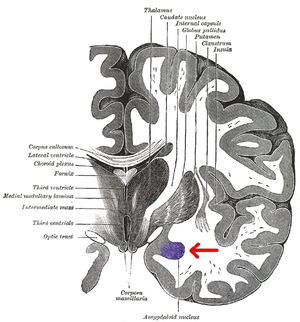

التركيب

The regions described as amygdala nuclei encompass several structures of the cerebrum with distinct connectional and functional characteristics in humans and other animals.[4] Among these nuclei are the basolateral complex, the cortical nucleus, the medial nucleus, the central nucleus, and the intercalated cell clusters. The basolateral complex can be further subdivided into the lateral, the basal, and the accessory basal nuclei.[5][6][7]

Anatomically, the amygdala [8] and more particularly its central and medial nuclei,[9] have sometimes been classified as a part of the basal ganglia.